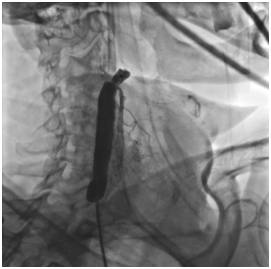

Операция проводилась правым феморальным доступом. Дистальный баллон системы позиционирован на расстоянии 1 см дистальнее бифуркации, в проксимальный отдел пНСА. Проксимальный баллон системы позиционирован в дистальном отделе пОСА. Последовательно произведено

раздувание дистального (в наружной сонной артерии) и проксимального (в общей сонной артерии) баллонов системы с перекрытием кровотока по целевому сосуду.

Проведение проводника за зону окклюзии с последующей реканализацией окклюзии баллонным катетером d=3 L=20 мм инфляцией 14 атм.

В область остаточного стеноза позиционирован и имплантирован самораскрывающийся каротидный стент с «закрытой ячейкой» d= 8-6 L=40 мм, с последующей постдилатацией стентированного сегмента баллонным катетером d=6 L=20 мм инфляцией 8 атм.